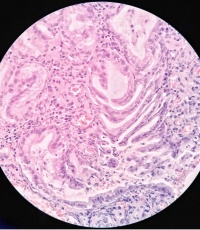

胃角溃疡活检

性别年龄53临床诊断

一般病史胃角溃疡

标本名称活检

大体所见灰白

粘膜慢性活动性炎

没有恶性病变。

考虑:急性炎症修复性反应。

• 王新安:  再看图12与13,腺癌不排除。

第一次的发图3那样的区域还是有些让人放心不下,片子这个颜色,分辩起有来点困难,建议重切重染,看清楚了再发,